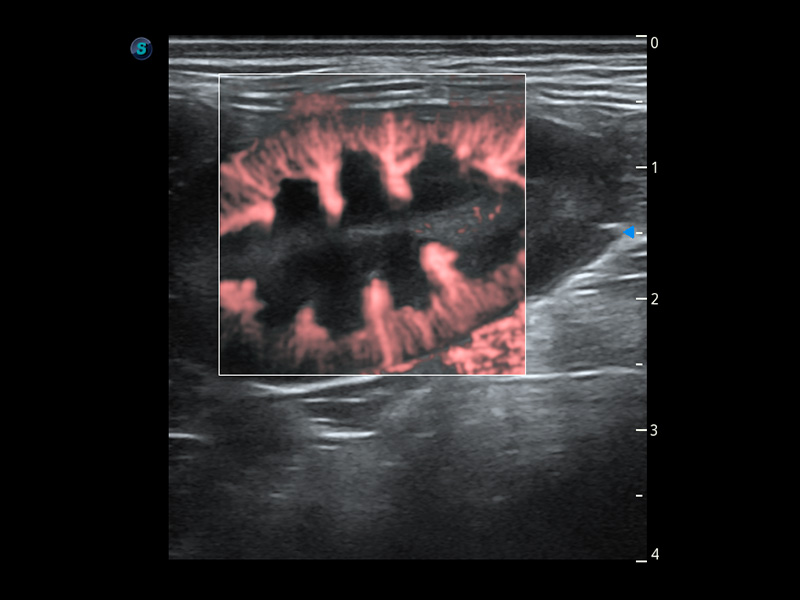

ProPet 60 作为一款高端台式动物超声设备,为动物医生的日常诊断提供了一系列贴合动物临床需求、解决临床实际问题的高级成像功能。凭借全系列高清探头,满足医生对腹部、心脏、生殖、浅表、肌骨等成像的所有需求,切实帮助您提升检查效率,提高诊断信心。

动物是人类最亲密的朋友和最值得信赖的伙伴。狗万官方网站也一直致力于探索动物专用的超声影像解决方案。 全新推出的ProPet系列,是狗万官方网站在动物超声影像智能化、专业化、精准化的一次跨越式革新。动物不能用言语来表述自己的不适,通过超声影像,ProPet系列搭建了动物医生与不同物种沟通的“桥梁”,为动物医生注入了“治愈之力”。